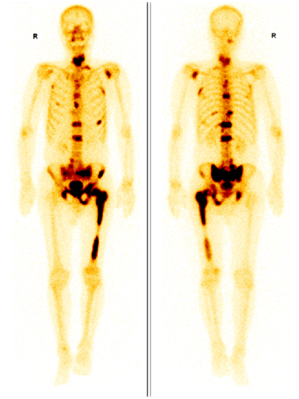

全身骨顯像(Whole Body Bone Scan,WBBS),又稱為骨掃描,是將放射性核素標(biāo)記的顯像劑(一般為99mTc-MDP)注射到體內(nèi),顯像劑隨血流到達全身骨骼,通過離子交換、化學(xué)吸附和與骨的有機成分結(jié)合的方式沉積到骨骼中,利用單光子發(fā)射型計算機斷層掃描儀(SPECT)得到顯像劑在全身骨骼分布情況,從而得到全身骨骼的圖像。

圖示,前列腺癌多發(fā)骨轉(zhuǎn)移,圖中深顏色區(qū)域為轉(zhuǎn)移灶。

骨組織中的有機物如未成熟的骨膠原對顯像劑有較高的親和力,因此在成骨活性增強的區(qū)域(骨折修復(fù)、骨腫瘤、成骨性骨轉(zhuǎn)移灶等),顯像劑會明顯濃聚,形成“熱區(qū)”。與X線、CT、磁共振等解剖影像相比,全身骨顯像是功能影像,可以比解剖影像更早發(fā)現(xiàn)病變。

例如上圖,左圖好比常規(guī)CT、MR等解剖影像,細(xì)節(jié)清晰,但不能發(fā)現(xiàn)形態(tài)正常和輕度異常的病變;右圖類似功能影像,直接將病變點亮,一目了然。